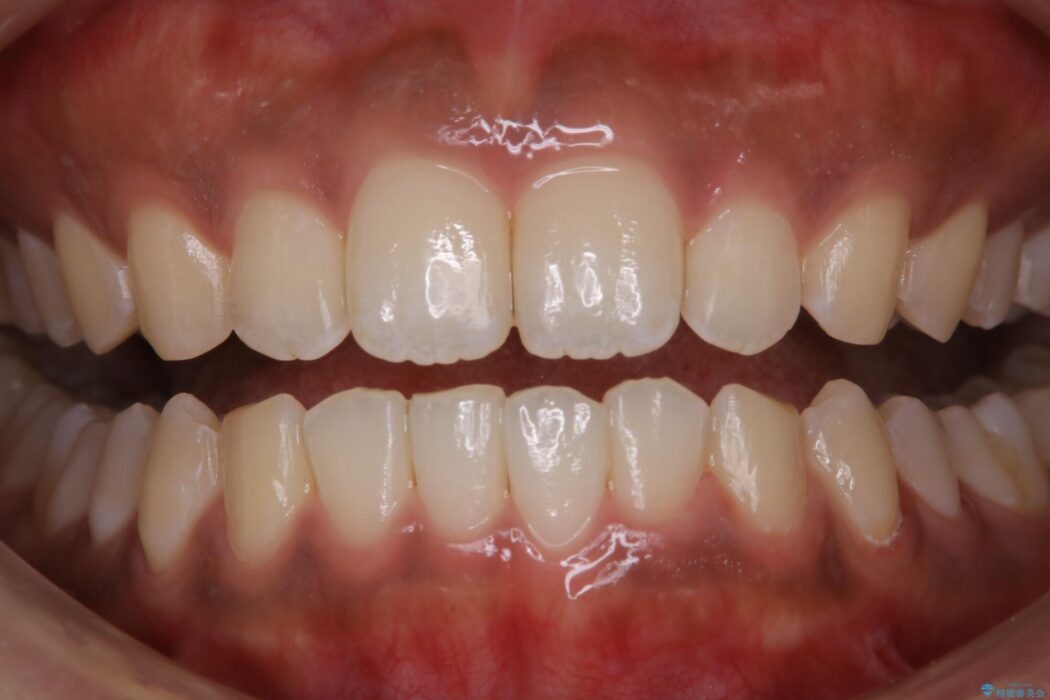

【20代女性】タバコのヤニ(ニコチン、タール)を徹底的に除去

タバコによって付着したステインを綺麗にしたいとのことで来院されました。

ステインがこびりついていたため、PMTC60分コースを行いました。

治療後について

タバコに含まれているタールが歯の黄ばみの原因になります。その黄ばみなどを、無理に落とそうとしたりすると歯の表面に傷がついてしまったり余計に汚れがつきやすい状態になることがあります。

PMTCでは、専門の機材を使用し、歯の表面の凸凹にミネラルを補給して、ツルツルの表面に仕上げます。定期的にPMTCを行うことにより、歯質の強化になり着色がつきにくい状態になります。